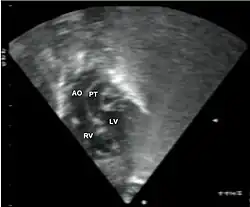

Additional images

Abbreviations: LV and RV=left and right ventricle, PT=pulmonary trunk, VSD=ventricular septal defect, PS=pulmonary stenosis.